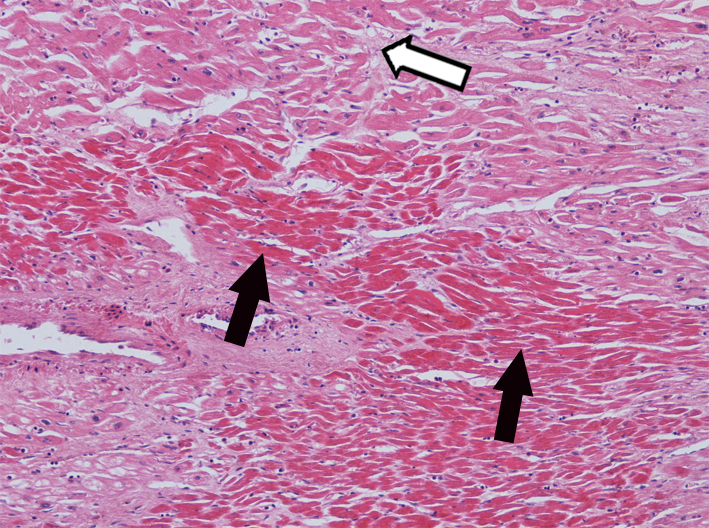

6.急性心肌梗死